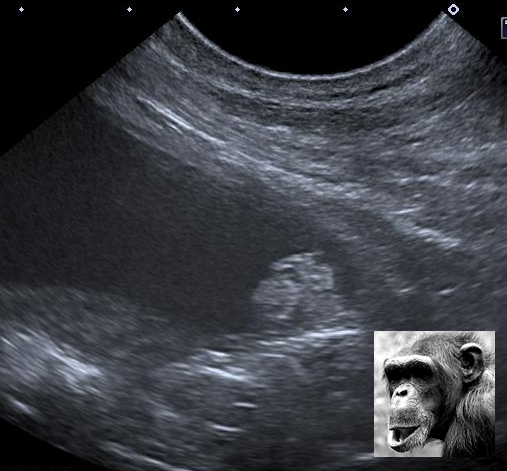

Un chimpanzé dans la vessie

Un proverbe africain dit «Si ton lit bouge et fait une bosse, c’est qu’il y a un singe dedans.» Et bien dans ce cas-ci, on peut dire «Si la vessie contient un singe qui fait une bosse, c’est qu’il y a une tumeur dedans» !

En tous cas, la singe est fantastique. Nice catch Guy!

Très beau le chimpanzé urinaire! J’en suis un peu jaloux… Je vais travailler fort pour vous trouver des animaginations en 2013 (une résolution de plus!).